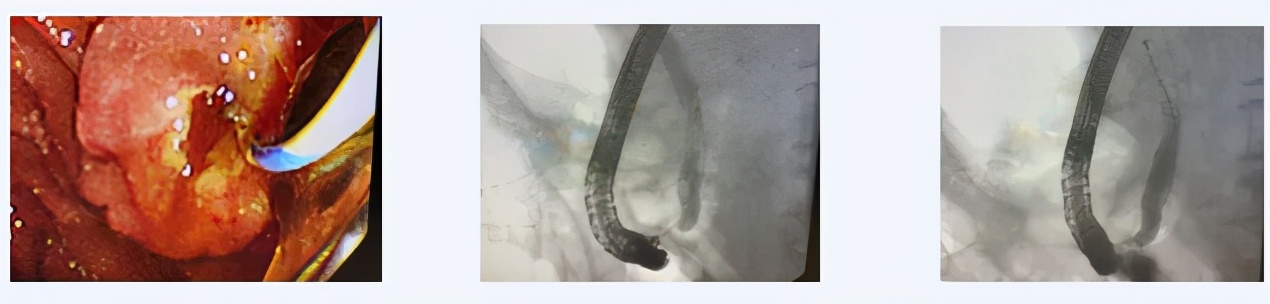

患者90岁,退役老红军,因“心力衰竭,休克状态”收入西青医院心内科,入院后进一步评估病情,确诊为“胆总管结石,急性胆管炎,感染性休克,心力衰竭”,普通外科主治医师王利军会诊后建议转外科病区治疗。该患者转入外科后,完善检查积极抗感染抗休克治疗评估患者病情,考虑患者相关症状均与胆系结石梗阻所致的感染密切相关,考虑到患者高龄,心衰IV级,休克状态,无法耐受手术,且患者危急重症,无法进行全麻治疗,经沟通建议首选局麻下ERCP微创治疗。随后在天津市南开医院内镜专家的指导下,与内镜室护理团队在介入室局麻下,通过十二指肠镜成功为该患者清除胆总管内多发结石放置BD管引流胆汁,解除梗阻后患者病情迅速稳定,恢复良并好出院。

患者75岁,女性,患者因“胆总管结石,胆道感染,急性胆囊炎,胆囊结石”急症收治西青医院,既往右肾恶性肿瘤史,全身多处转移,腹腔内多发转移,同时合并心脏支架术后,肾功能不全等情况。主治医师胡石甫结合患者肿瘤晚期病史,无法耐受手术情况,建议患者首选ERCP解除胆道梗阻,进行缓解症状治疗。通过抗炎对症治疗后,在天津市南开医院内镜专家的指导下,王金伟医生再次与内镜室护理团队协作在介入室局麻下通过十二指肠镜成功为该患者放置胆道支架改善梗阻,遂后患者病情恢复良好,日前已好转出院。

经内镜逆行胰胆管造影(ERCP)是指将十二指肠镜插至十二指肠乳头,由内镜活检管道插入造影导管至胆管或胰管,经造影导管注射造影剂作X 线胰胆管造影。此操作主要适用于1、疑有胆总管结石、肿瘤、炎症或梗阻性黄疸原因不明者;2、胆囊切除术后或胆总管术后胆系症状复发;3、怀疑胰腺肿瘤、慢性胰腺炎或复发性胰腺炎缓解期;4、十二指肠乳头或壶腹部肿瘤;5、原因不明上腹痛,怀疑胆胰疾病;6、其他胆系疾病需行内镜下治疗者。